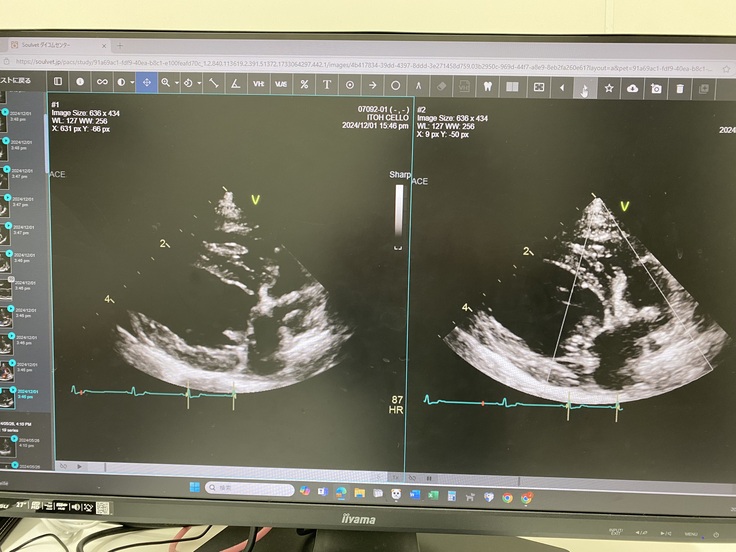

血液の逆流がなく、弁の形もとっても綺麗だから再発する可能性はかなり低いと仰ってました😊✨️